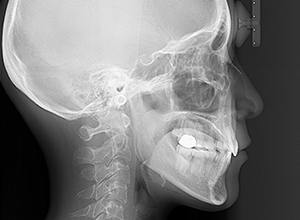

初診時

X-Ray

X-Ray所見

セファロ所見 下顎枝、骨体部共に大きくしっかりとしており下顎角は平均的であった。中顔面部の高さは高く奥行きあもり、上下顎骨は調和のとれた骨格形態をしていた。